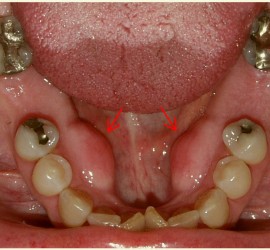

Реактивное тяжелое общее состояние организма, наступающее вскоре после травмы. Развивается в связи с нарушением нервной регуляции жизненных процессов и проявляется тяжелыми расстройствами гемодинамики, дыхания и обмена веществ. Этиология. Тяжелые ранения и повреждения, сопровождающиеся обширным размозжением тканей, ампутацией (отрыв) органов лица, массивными ушибами и сдавлениями челюстно- лицевой области, кровопотерей и кислородным […]